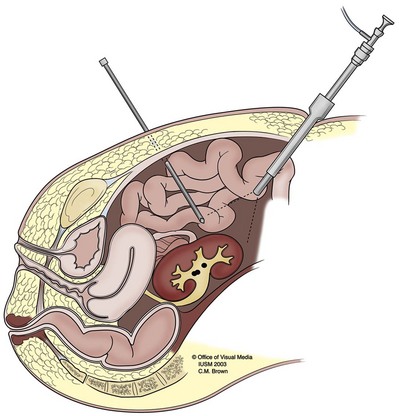

For patients with larger calculi or for those who demonstrate evidence of poor urine drainage, PNL should be the primary approach. The results of PNL for patients with calculi in a horseshoe kidney are generally superior to those achieved with SWL, with an average stone-free rate of 84% (range, 75% to 100%) (Esuvaranathan et al, 1991; Jones et al, 1991a; Al-Otaibi and Hosking, 1999; Raj et al, 2003; Shokeir et al, 2004). The optimal point of entry for these kidneys is through a posterior calyx, which is typically more medial than in the normal kidney because of the altered renal axis and rotation associated with the midline fusion (Fig. 48–5). Except in the isthmus of the horseshoe kidney, where the vascular supply can vary, vessels tend to enter the kidney anteriorly. An upper pole collecting system puncture is often appealing because the entire kidney is usually subcostal. In most cases the lower pole calyces are anterior and inaccessible percutaneously. During PNL the flexible nephroscope often aids in accessing stones within anteromedial calyces, which may be difficult to reach with a rigid nephroscope.

Figure 48–5 Antegrade nephrostogram performed after percutaneous nephrolithotomy of a horseshoe kidney via an upper pole access. Note the subcostal nature of the access and the unique calyceal orientation inherent in a horseshoe kidney.